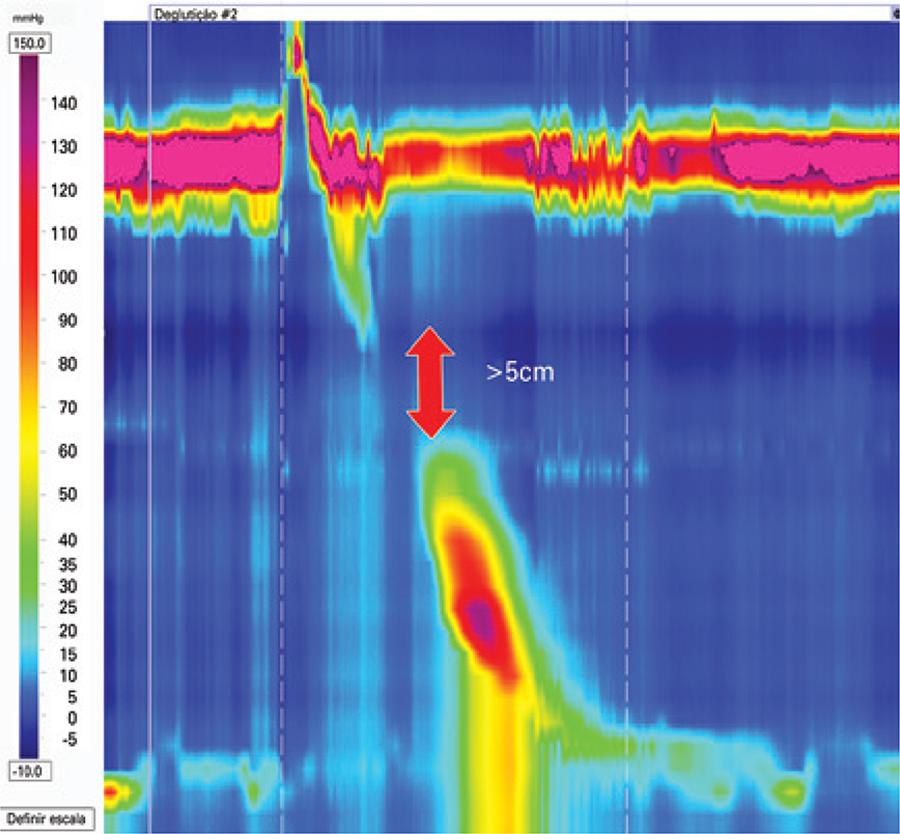

Apresentação em imagens da Classificação de Chicago versão 3.0 das doenças da motilidade esofagiana

A manometria de alta resolução mudou vários paradigmas da motilidade digestiva. A Classificação de Chicago, na versão 3.0, definiu critérios manométricos para as doenças da motilidade esofagiana. O presente artigo é um atlas das dismotilidades descritas. Tipos de acalásia, obstrução ao nível da junção esofagogástrica, contrações ausentes, espasmo esofagiano distal, esôfago hipercontrátil, motilidade esofagiana ineficaz e peristalse fragmentada são mostradas em traçados de manometria de alta resolução.